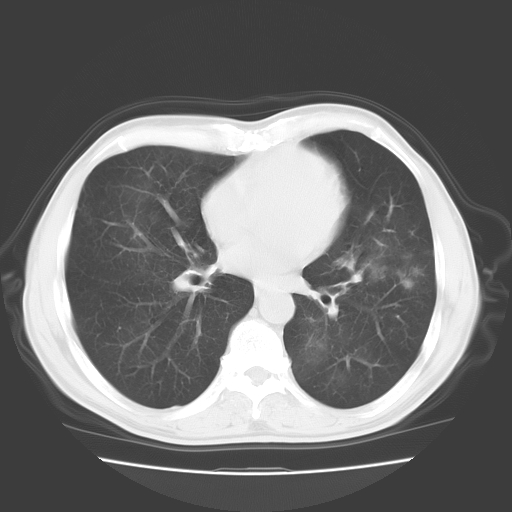

以下是引用随光逐影在2008-11-20 23:02:00的发言:[br]1)考虑左肺上叶周围型肺癌可能性大。2)两肺散在性肺泡积血。[br][br][本贴已被 随光逐影 于 2008-11-20 23:09:31 修改过]

以下是引用drzhang8888在2008-11-20 22:20:00的发言:[br]密集的短毛刺,血管集束,胸膜凹陷,周边型肺癌可能性大,另双肺多发磨玻璃影,考虑感染

以下是引用流浪星在2008-11-20 22:28:00的发言:[br]左肺上叶近外围区见一类圆形结节影,毛刺征、胸膜尾征阳性,临近肺组织见多发渗出灶。考虑1,炎症性病变。 2.周围性肺癌。建议抗炎治疗后复查。

以下是引用qc80012345在2008-11-21 5:53:00的发言:[br]支持;周围型肺癌诊断。增强扫描。